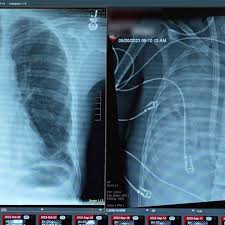

The patient was admitted in 2023 after contracting Influenza B, which progressed to acute respiratory distress syndrome (ARDS) and necrotizing pneumonia.

Despite being on a ventilator and extracorporeal membrane oxygenation (ECMO), the patient developed refractory septic shock, suffered multiple cardiac arrests, and experienced kidney failure. Doctors reported that the infection could not be controlled while the severely damaged lungs remained in his body, according to the journal Med.

Dr Ankit Bharat, chief of thoracic surgery at Northwestern University Feinberg School of Medicine, and his team performed a bilateral pneumonectomy, removing both lungs to eliminate the source of infection.

To replace lung function, the team developed a custom extracorporeal total artificial lung (TAL) system. The device oxygenated the patient’s blood, removed carbon dioxide, and helped regulate circulation to support heart function.

Within 48 hours, the patient’s condition began to improve, with blood pressure stabilising and kidney function returning to normal. Doctors were able to discontinue medications supporting his heart. Tests on the removed lungs later confirmed irreversible damage, underscoring the need for a transplant.

The patient was placed on the waiting list for a double-lung transplant and received donor organs shortly afterward. More than two years later, he has normal lung function and shows no signs of organ rejection.